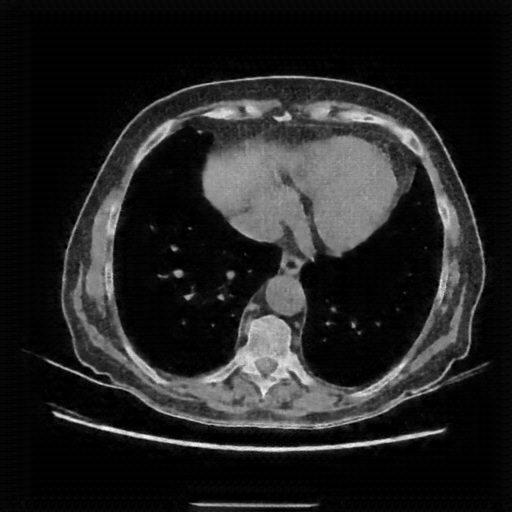

Image Grid

4Γ—3 grid: Rows show different image types (Original NATIVE, Reconstructed NATIVE, Original VENOUS, Generated VENOUS), Columns show windowing techniques (No Window, Lung Window, Mediastinum Window)

Lung window (WL -600, WW 1500 β†’ Low βˆ’1350, High +150)

Original NATIVE CT scan (input)

Reconstructed NATIVE CT scan (cycle consistency)

Original VENOUS CT scan

Generated VENOUS CT scan (A→B translation)